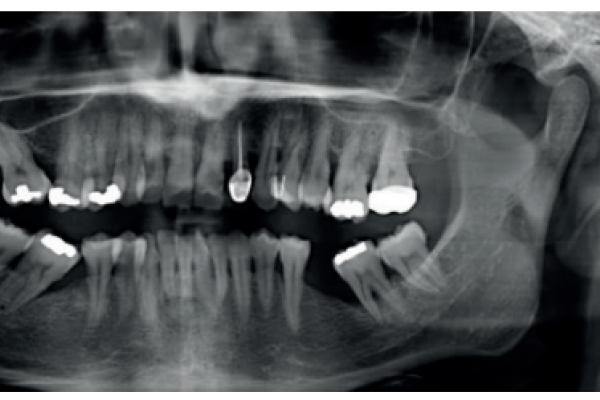

Tratamiento con implantes dentales en pacientes irradiados por cáncer de cabeza y cuello. Parte 1

Tratamiento con implantes dentales en pacientes irradiados por cáncer de cabeza y cuello. Parte 2